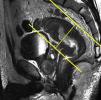

Tras el localizador inicial es recomendable realizar 3 secuencias rápidas de disparo único (single shot) ponderadas en T2 en los 3 planos para tener una mejor visión de la región a explorar y una mayor aproximación al área afectada. A continuación han de emplearse las secuencias de alta resolución FSE ponderadas en T2. En primer lugar ha de obtenerse una serie en plano sagital estricto de todo el mesorrecto que, además de aportar información para el diagnóstico (extensión cráneo-caudal del tumor y grado de infiltración), debe servir para planificar las demás secuencias con precisión. Seguidamente han de obtenerse planos perpendiculares y paralelos al eje longitudinal del recto que incluyan el mesorrecto en toda su extensión, desde el promontorio del sacro hasta el margen anal y desde el septo urogenital hasta el sacro (figs. 7 y 8). El objetivo de estas secuencias es evaluar posibles adenopatías mesorrectales y estudiar la posibilidad de aplicar implantes. Llegados a este punto, según el tercio del recto en estudio, es necesario obtener planos oblicuos directamente sobre la masa tumoral:

Han de obtenerse planos axiales oblicuos que cubran el tumor en toda su extensión y queden orientados perpendicularmente a su eje cráneo-caudal en el plano sagital (fig. 9). Las imágenes resultantes permiten evaluar el propio tumor y la afectación de la pared rectal y del mesorrecto, así como la afectación de las estructuras y órganos pélvicos.